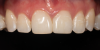

(8.) Posttreatment photograph of the completed direct composite veneer. (The photographs for the case depicted in Figure 6 through Figure 8 were provided by William “Bud” Mopper, DDS, MS.)

Figure 8

(6.) Pretreatment photograph of an intrinsically stained tooth.

Figure 6

(7.) A pink opaquer was placed prior to the placement of composite.

Figure 7

The degree of invasiveness of a composite veneer is dependent on the clinical scenario. In the case of an intrinsically discolored tooth, the tooth may have to be prepared to create room for the restorative materials. By virtue of composite resin's inherent optical properties, it has a limited ability to conceal discoloration. The application of a thin layer of an opaquer (eg, Creative Color® Opaquer and Creative Color® Pink Opaque, Cosmedent; Constic [Opaque-White], DMG; IPS Empress® Direct Opaque, Ivoclar; Estelite Color® [Pink Opaque], Tokuyama) prior to the placement of the composite can provide an alternative to placing a thicker layer of composite and reduce the amount of tooth structure that needs to be prepared. Opaquers are low-viscosity, highly pigmented resins that contain metal oxides. They are ideally suited for cases in which dark tooth structure needs to be blocked out prior to the placement of composite. They come in many colors, including but not limited to pink, white, and tooth colored. By virtue of their opacity, opaquers will raise the value of restorations. On the other hand, if a material that is too translucent is applied, it may appear grey. Opaquers can be applied after the bonding agent is applied and cured. They are often applied in multiple layers, typically with a brush, and cured after each layer is placed. They can also be applied between layers of composite. Clinicians should consult the manufacturer's recommendations to determine the layering technique of their chosen opaquer. However, as aforementioned, excessive application of opaquer may result in a tooth that is of considerably higher value or far more opaque than its adjacent teeth. Once the desired amount of opaquer has been placed, composite is then placed as the final restorative layer (Figure 6 through Figure 8).